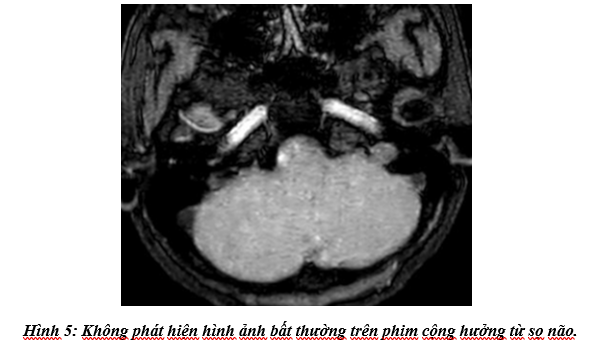

Cộng hưởng từ sọ não: Không phát hiện tổn thương bất thường.